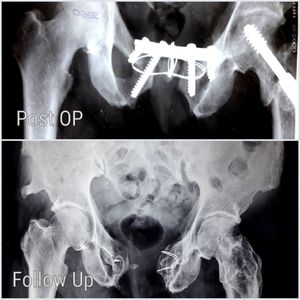

Open Book Repair

Patient presented following a RTA. Open book fracture has been repaired with screws and plate with a bone graft from the Right pelvic brim. Follow up Xray shows that the graft has been dissolved. ☹